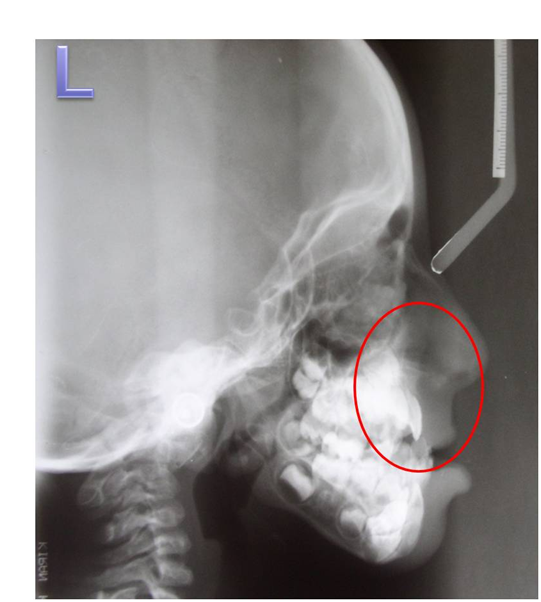

A 6 year old male patient, born of non consanguineous marriage, presented to our department with the complaint of deformed left ear since birth. It was associated with decreased hearing. Medical history revealed cleft palate surgery at the age of 1 year. The child was born of a full-term normal delivery and there was no history of any maternal illness during the pregnancy. But the child was cyanotic at the time of birth. All other family members were normal. Personal history showed normal bowel and bladder habits, undisturbed sleep. On General Examination, he was conscious and cooperative but had reduced grasping power and learning skills. Vital signs were within normal limits with no peripheral signs. Altered posture was noticed as the shoulder levels were not at same level (Figure 1). On extra oral examination, facial asymmetry was detected due to hallowing of left cheek and hypoplasia of left malar region, hypoplasia of maxillary bone and prognathic mandible (Figure 2). Facial profile was straight and leptoprosopic facial form was noticed. Deformed left ear and ear tags were seen on the right side (Figure 3). Hypertelorism was present. Ocular changes showed whitish area near outer canthus of both eyes approximately measuring 1X1cms suggestive of epibulbar dermoids on both sides (Figure 4). Cranial nerve examination revealed left facial nerve paralysis as he was unable to raise his eyebrows, no wrinkles on the forehead and unable to blow the cheeks on left side. On Intraoral Examination, palatal scar noticed suggestive of previous surgery for cleft palate and hard tissue examinations showed multiple root stumps and Angle’s class III malocclusion. The orthopantomograph showed mixed dentition (Figure 5) and the lateral cephalograph revealed malar and maxillary hypoplasia (Figure 6). We diagnosed the patient as a case of Goldenhar syndrome on the basis of multiple accessory tragi, ocular dermoids, hypoplastic malar process, facial nerve paralysis, mental retardation and skeletal abnormalities. Patient was referred for auricular surgery followed by ear prosthesis replacement.

Figure 6 Lateral cephalograph showing hypoplastic malar and maxillary bone.